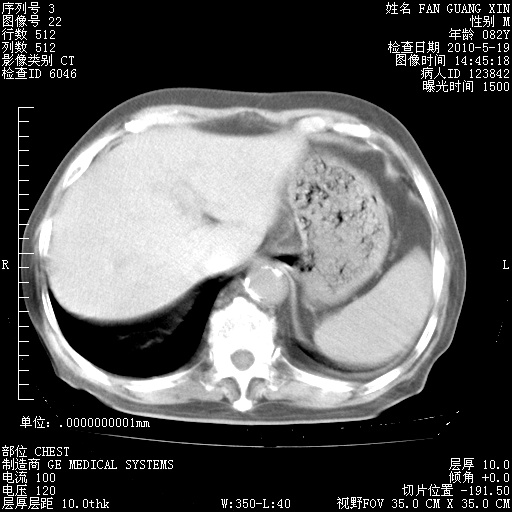

再治疗10天后的肺部CT

从白细胞总数和中性比例看好像合并感染。肺部纹理好像比上次多,支气管炎?其他感染?

阅读此次胸部CT,肺间质渗出性改变较入院时有吸收。目前从体温、白细胞、中性分叶明显增高,肯定存在细菌感染(发生医院感染哦,若无消化道及泌尿系统等感染的依据,肺部感染可能大)。若你院头孢哌酮舒巴坦钠耐药率较高,同意你的方案,若48小时体温仍高,可考虑使用碳青霉稀类抗菌药物,同时可予超声雾化、注意滴数时加大液体量。白蛋白33.30g/L较低哦,需加强营养等支持治疗。